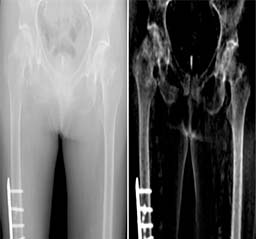

Department of Radiology

Introduction

The radiology department may also be called the X-ray or imaging department. It is the facility in the hospital where radiological examinations of patients are carried out, using the range of equipment listed above.

A radiologist Issues medical imaging such as x-ray, MRI, CT, ultrasound and angiography, to diagnose and treat human disease or injury.

"Departmental Photos"